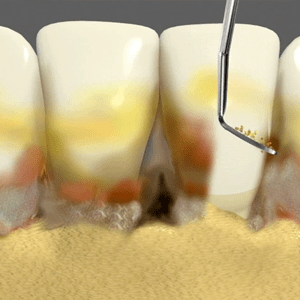

Scaling

Scaling is one of the most important processes in periodontal care which helps in curing gum diseases. The procedure involves removal of tarter from the tooth surface and roots. Periodontists use special instruments to clean the surface of the teeth. The instruments clean the gum pockets and reach the teeth roots to remove hardened tarter. Local anaesthesia may be used during the process to relieve patients from pain. The periodontist guides patients about routine maintenance and they may have to visit the dental practice frequently in order to keep the periodontal disease in control.